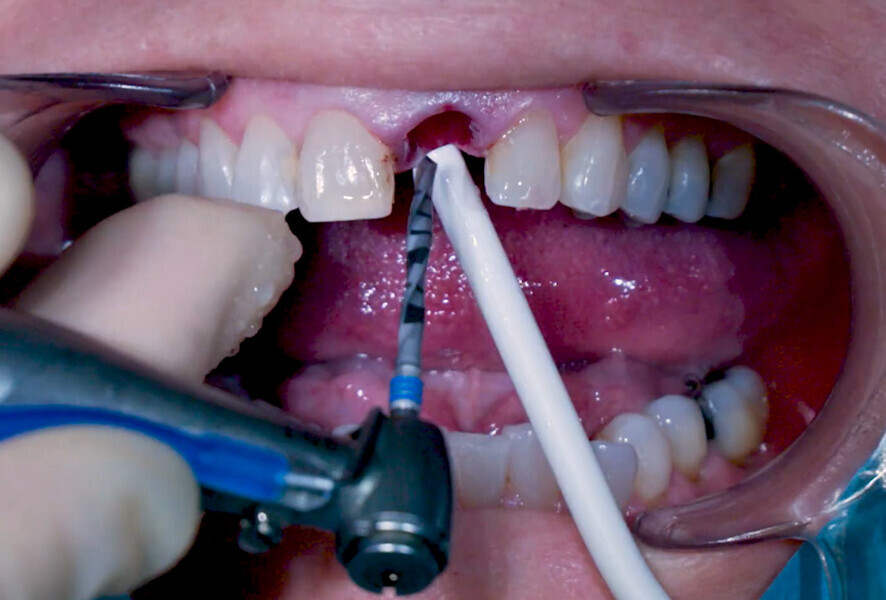

Fig. 17: Application of collacone (botiss

biomaterials).

Fig. 18: Biomaterial application finalised.